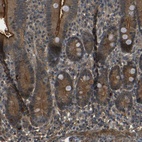

Immunohistochemical staining of human duodenum shows strong membranous and cytoplasmic positivity in glandular cells.